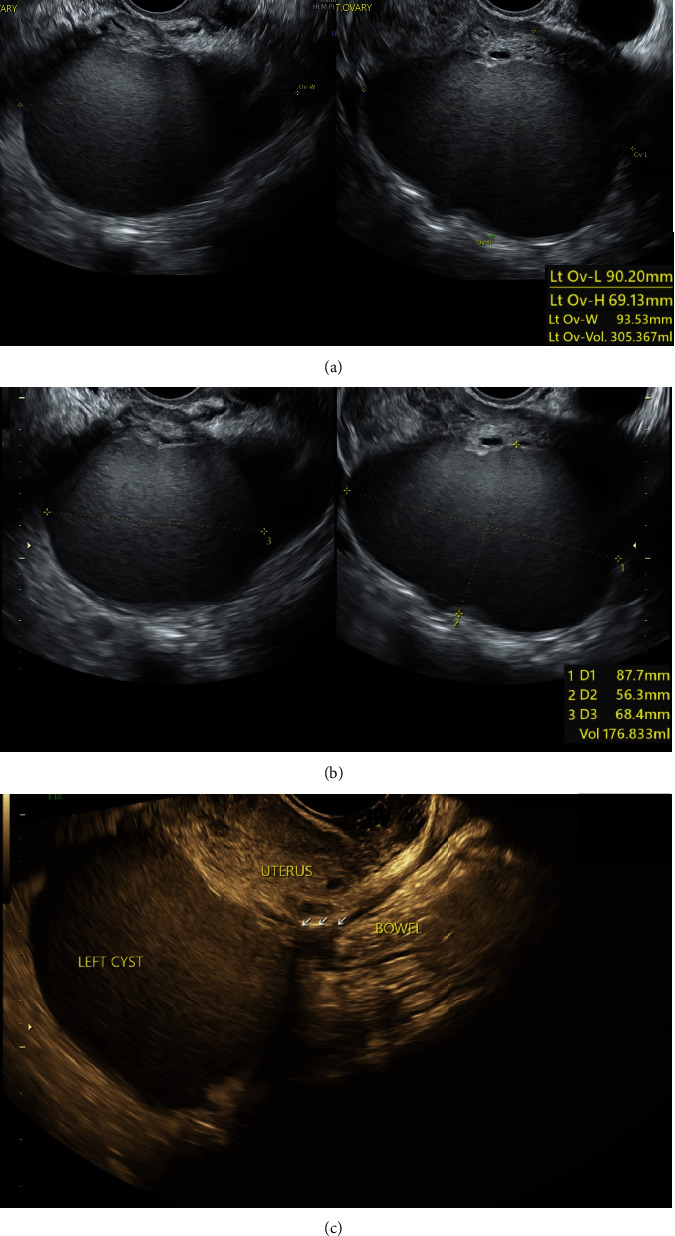

In the context of increased adoption of minimally invasive surgery for benign gynaecological conditions, this study underscores the paramount importance of patient safety. We explored the efficacy of indocyanine green (ICG), a fluorescent dye, in enhancing the visualisation of critical anatomical structures during complex laparoscopic procedures. Our methods involved the direct administration of ICG into the ureters for precise identification and dissection, as well as an innovative vaginal application to delineate the rectovaginal plane in cases with distorted pelvic anatomy. The study presented two cases: a laparoscopic hysterectomy for a multifibroid uterus and a case of advanced endometriosis with rectal involvement. Results indicated that ICG use significantly improved real-time visualisation of the ureters and the rectovaginal plane, which facilitated the surgeries and reduced the cognitive load on surgeons. There were no intraoperative complications, and the postoperative phase showed positive patient outcomes. In conclusion, the application of ICG in these laparoscopic surgeries proved to be a beneficial adjunct, suggesting its potential for broader application in benign gynaecological surgeries. Future research is warranted to explore additional uses of ICG, with a focus on enhancing patient safety and surgical efficacy.